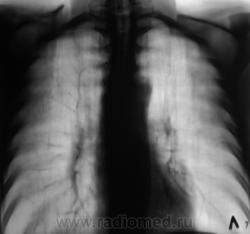

Рентгенограмма.

С двух сторон в верхних долях очаги. На вскидку tbs. А что с клиникой, анализами, анамнез.

Двусторонний очаговый туберкулез.

В s 1 -2 и глубоких отделах s6судя по срезам очаги,справа с включениями кальция,на фоне фоброзно измененного легочного рисунка

Коллеги, кто может, укажите стрелками на обзорной рентгенограмме очаги. Я не вижу.

Согласен, нежные дела и проглядеть легче легкого по бзорке, тем более там где зачастую не ждешь его)))